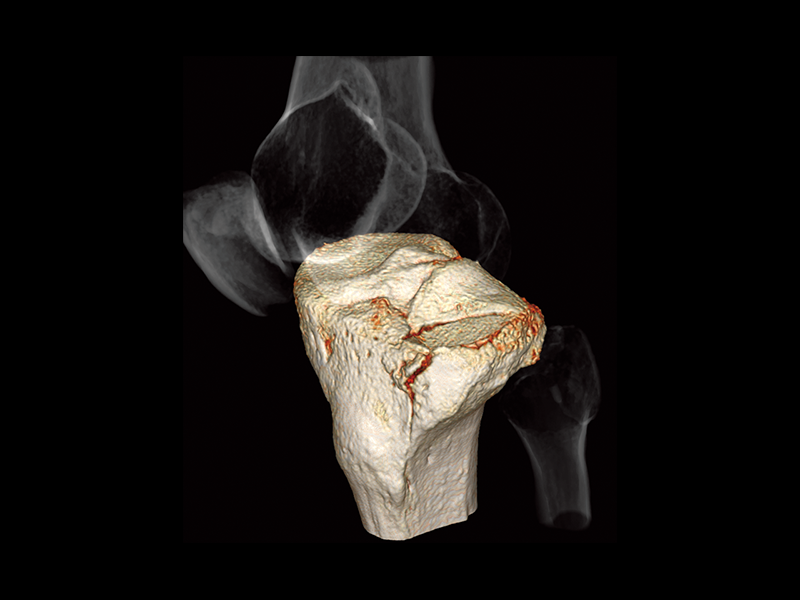

Tibial plateau fracture